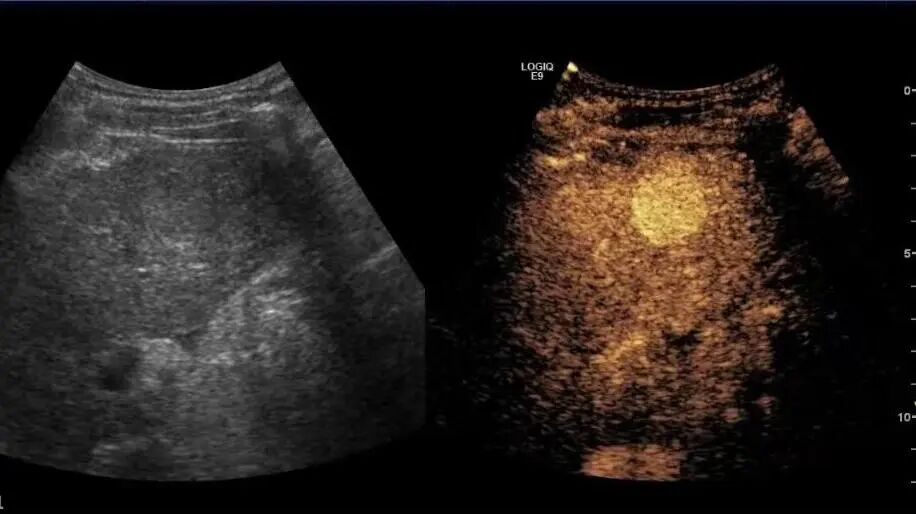

1月7日,贵州航天医院第91次晨读会由我院超声科医师杨向蓉作学术交流,她以“小微泡,大作用——右心声学造影”为题,详细讲解了右心声学造影的基本原理、适用情况、操作方式及心脏异常分流评估特点等内容,涵盖了该技术的实施条件、所用造影剂类型及多种激发试验方法,并通过多个病例图文资料分享了右心声学造影在相关症状病因探寻中的辅助角色,为临床评估提供了一种观察途径,有助于从循环角度了解某些症状的可能原因,在相应症状的病因分析中具有一定的参考意义。 贵州航天医院 超声科专家简介 吴艳辉 中共党员,超声科学科带头人,主任医师 专业擅长:从事超声诊断工作30余年,对心血管、小器官超声、超声引导下介入等具有丰富的临床经验。 胡大海 超声科主任,副主任医师 专业擅长:从事超声工作20余年,对心血管、外周血管、浅表器官、成人颅脑、超声造影诊断及超声引导下介入等具有丰富的临床经验。 骆科美 中共党员,超声科副主任医师 专业擅长:从事超声诊断工作30余年,对胎儿心脏及颅脑、妇产超声诊断、盆底超声等具有丰富的临床经验。 刘 敏 超声科副主任医师 专业擅长:从事超声诊断工作20余年,对妇产科超声、心脏血管超声诊断具有丰富的临床经验。 韩锡铁 超声科副主任医师 专业擅长:从事超声诊断近20年,对心血管、外周血管、浅表器官、肌骨神经超声诊断具有丰富的临床经验。 杨向蓉 中共党员,超声科主治医师 专业擅长:从事超声诊断工作16年,擅长心血管、浅表器官、盆底、腹直肌超声、右心声学造影及超声引导介入等技术。 贵州航天医院超声科简介 基本情况 贵州航天医院超声科配备多种超声检查设备(飞利浦彩超(IU-22、IU-Elite、EPIQ5、EPIQ7),迈瑞彩色超声(ResonaI9T、RechoR9、Resona I9、DC-8)、GE-VolusonE8、汕头SIUIAPogee6800、床旁彩色超声诊断仪等),设有心血管诊室、外周血管诊室、妇产科诊室、腹部诊室、绿色通道、浅表小器官等检查室。 诊疗范围 科室业务覆盖腹部、泌尿、妇科、产科(常规、NT筛查、系统筛查及高危妊娠监护)、成人心脏、外周血管、浅表器官(包含甲状腺、乳腺、阴囊、眼睛等)、颅脑(小儿颅脑、成人帕金森辅助筛查)、小儿肺超、超声造影、盆底、腹直肌、肌骨神经等检查及各种超声介入引导。 专科特色 四肢血管超声检查、产前系统筛查及超声监护、超声造影检查技术、介入超声临床应用、经颅脑实质超声辅助筛查诊断帕金森病、小儿髋关节筛查、女性性早熟超声诊断、盆底、腹直肌超声检查等。 NT超声检查 超声介入引导 肝脏超声造影 甲状腺造影 颅脑超声帕金森辅助检查 乳腺超声造影 上肢动静脉造瘘超声检查 双胎超声筛查 下肢血管超声检查 右心造影 end